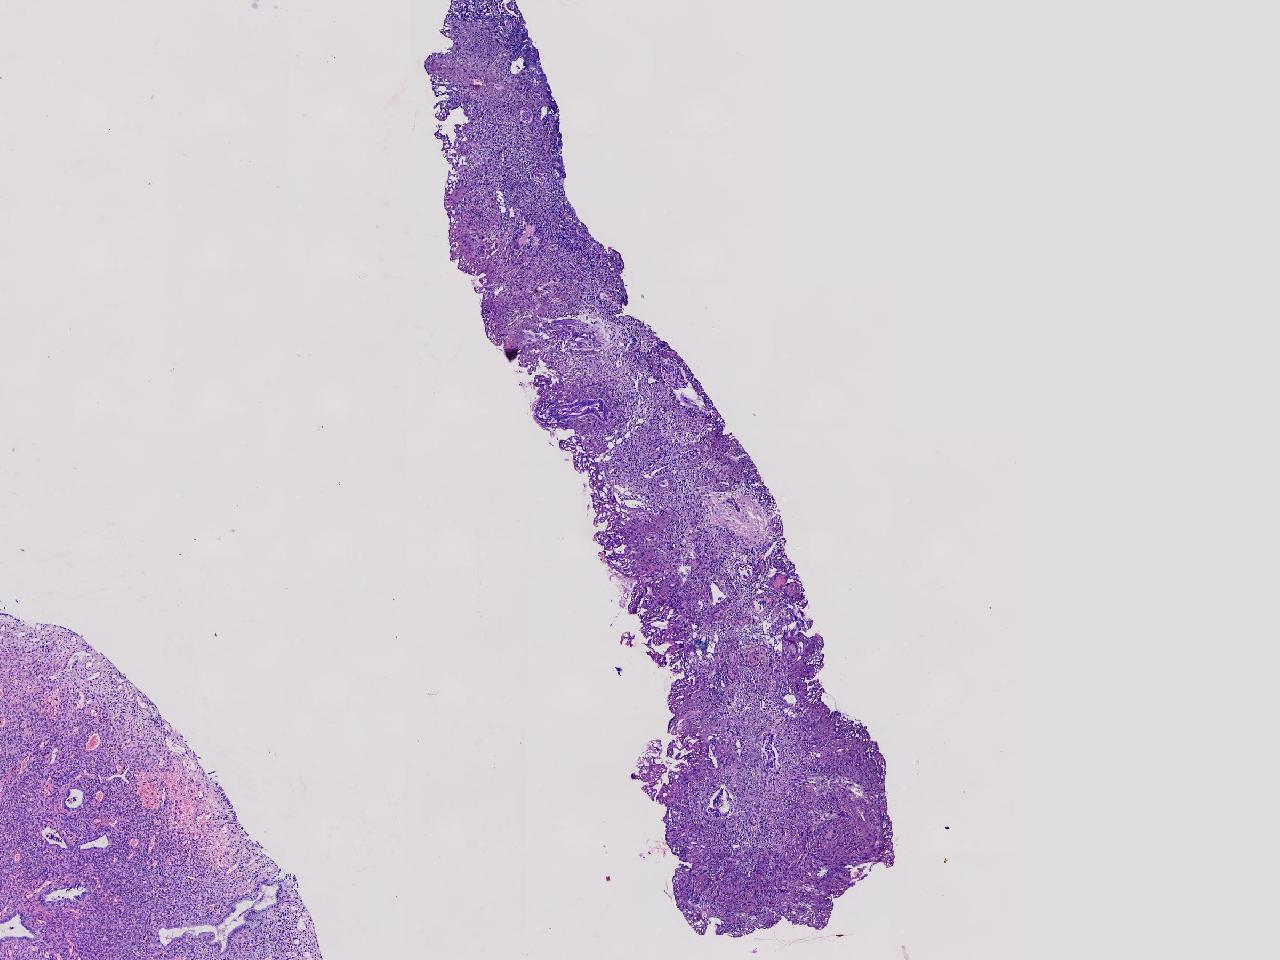

宫腔息肉?

性别

女

年龄

56岁

彩超示宫腔内见5x3ml的团状偏强回声结节,边界清。

灰粉色不整形软组织多块,0.5X0.3X0.3厘米。

首先考虑子宫内膜息肉,有些区域间质细胞较密,找找看有没有核分裂。

彩超提示强声团体积不小,待完整切除送检再综合诊断。